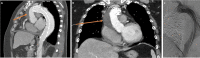

Case report: We present the case of a 49-year-old male who underwent urgent redo-surgery for total arch replacement and de-branching following recent replacement of the ascending aorta for acute type-A dissection, where an AMDS stent was deployed. The patient underwent total arch replacement with a stented tri-furcate prosthesis and de-branching of arch vessels with the stent landed inside the previous AMDS, to good effect.